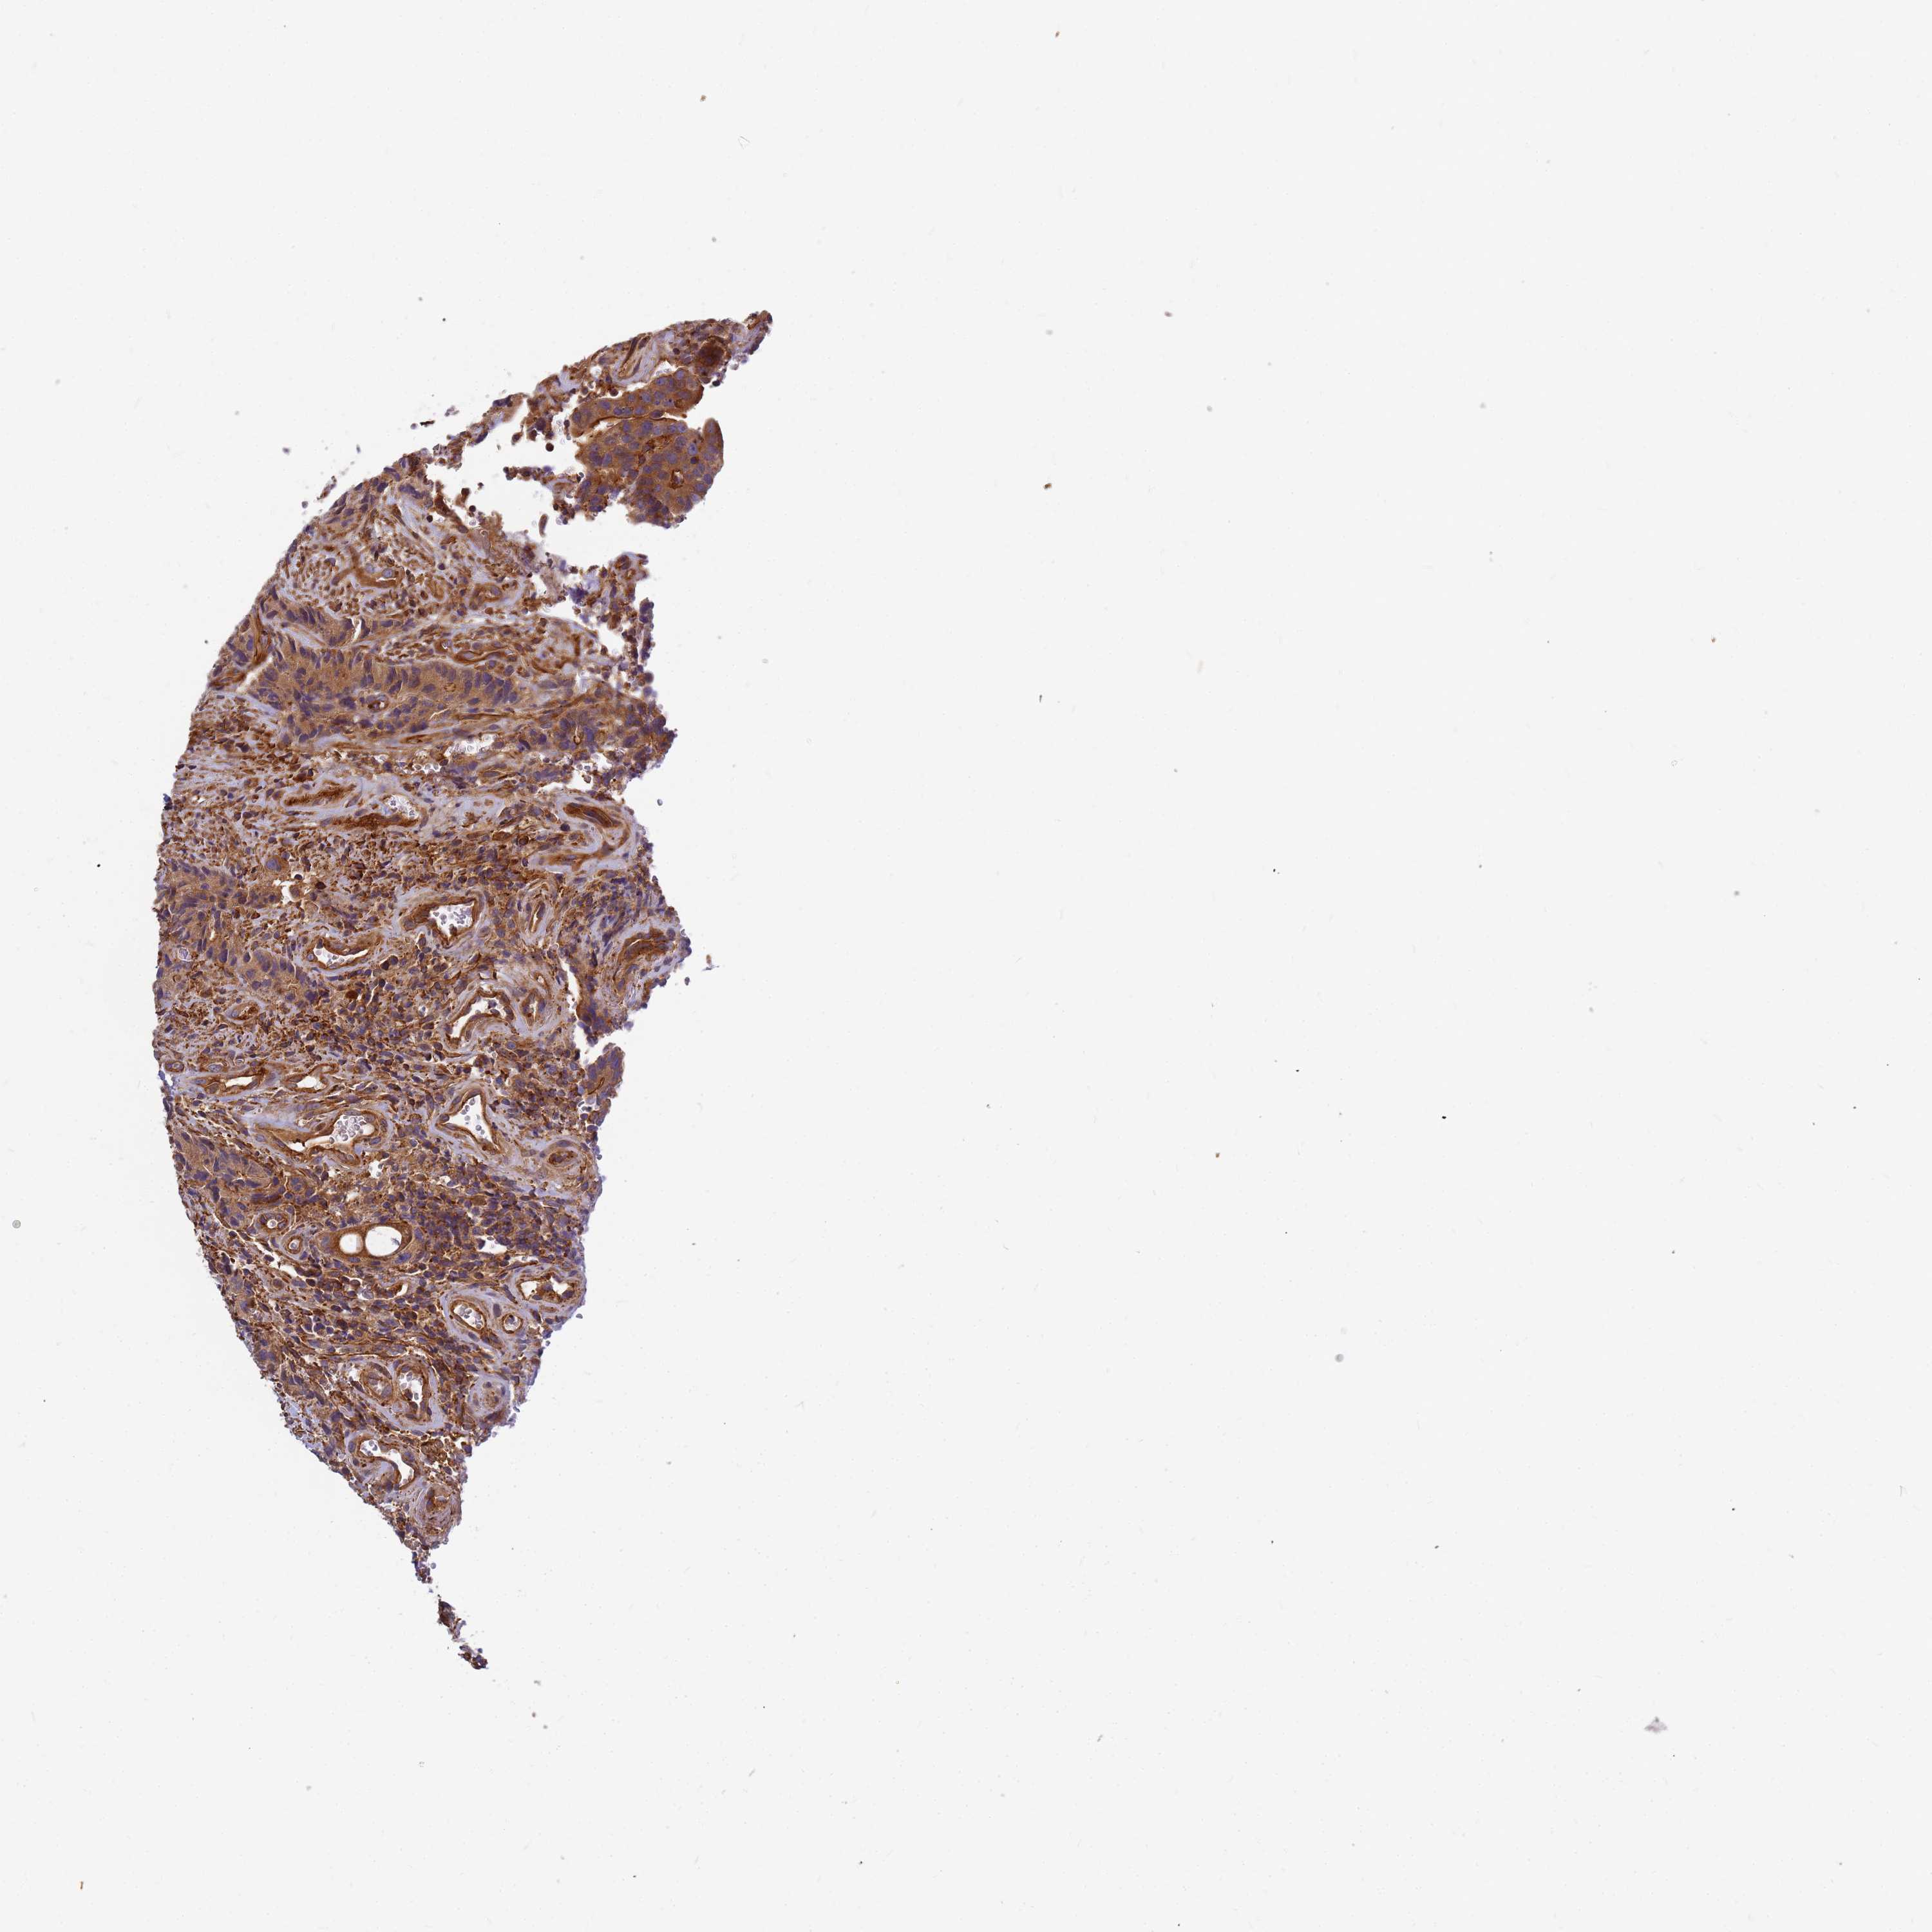

CANCER COLORECTAL CANCER Show tissue menu

Colorectal cancer

Colon adenocarcinoma